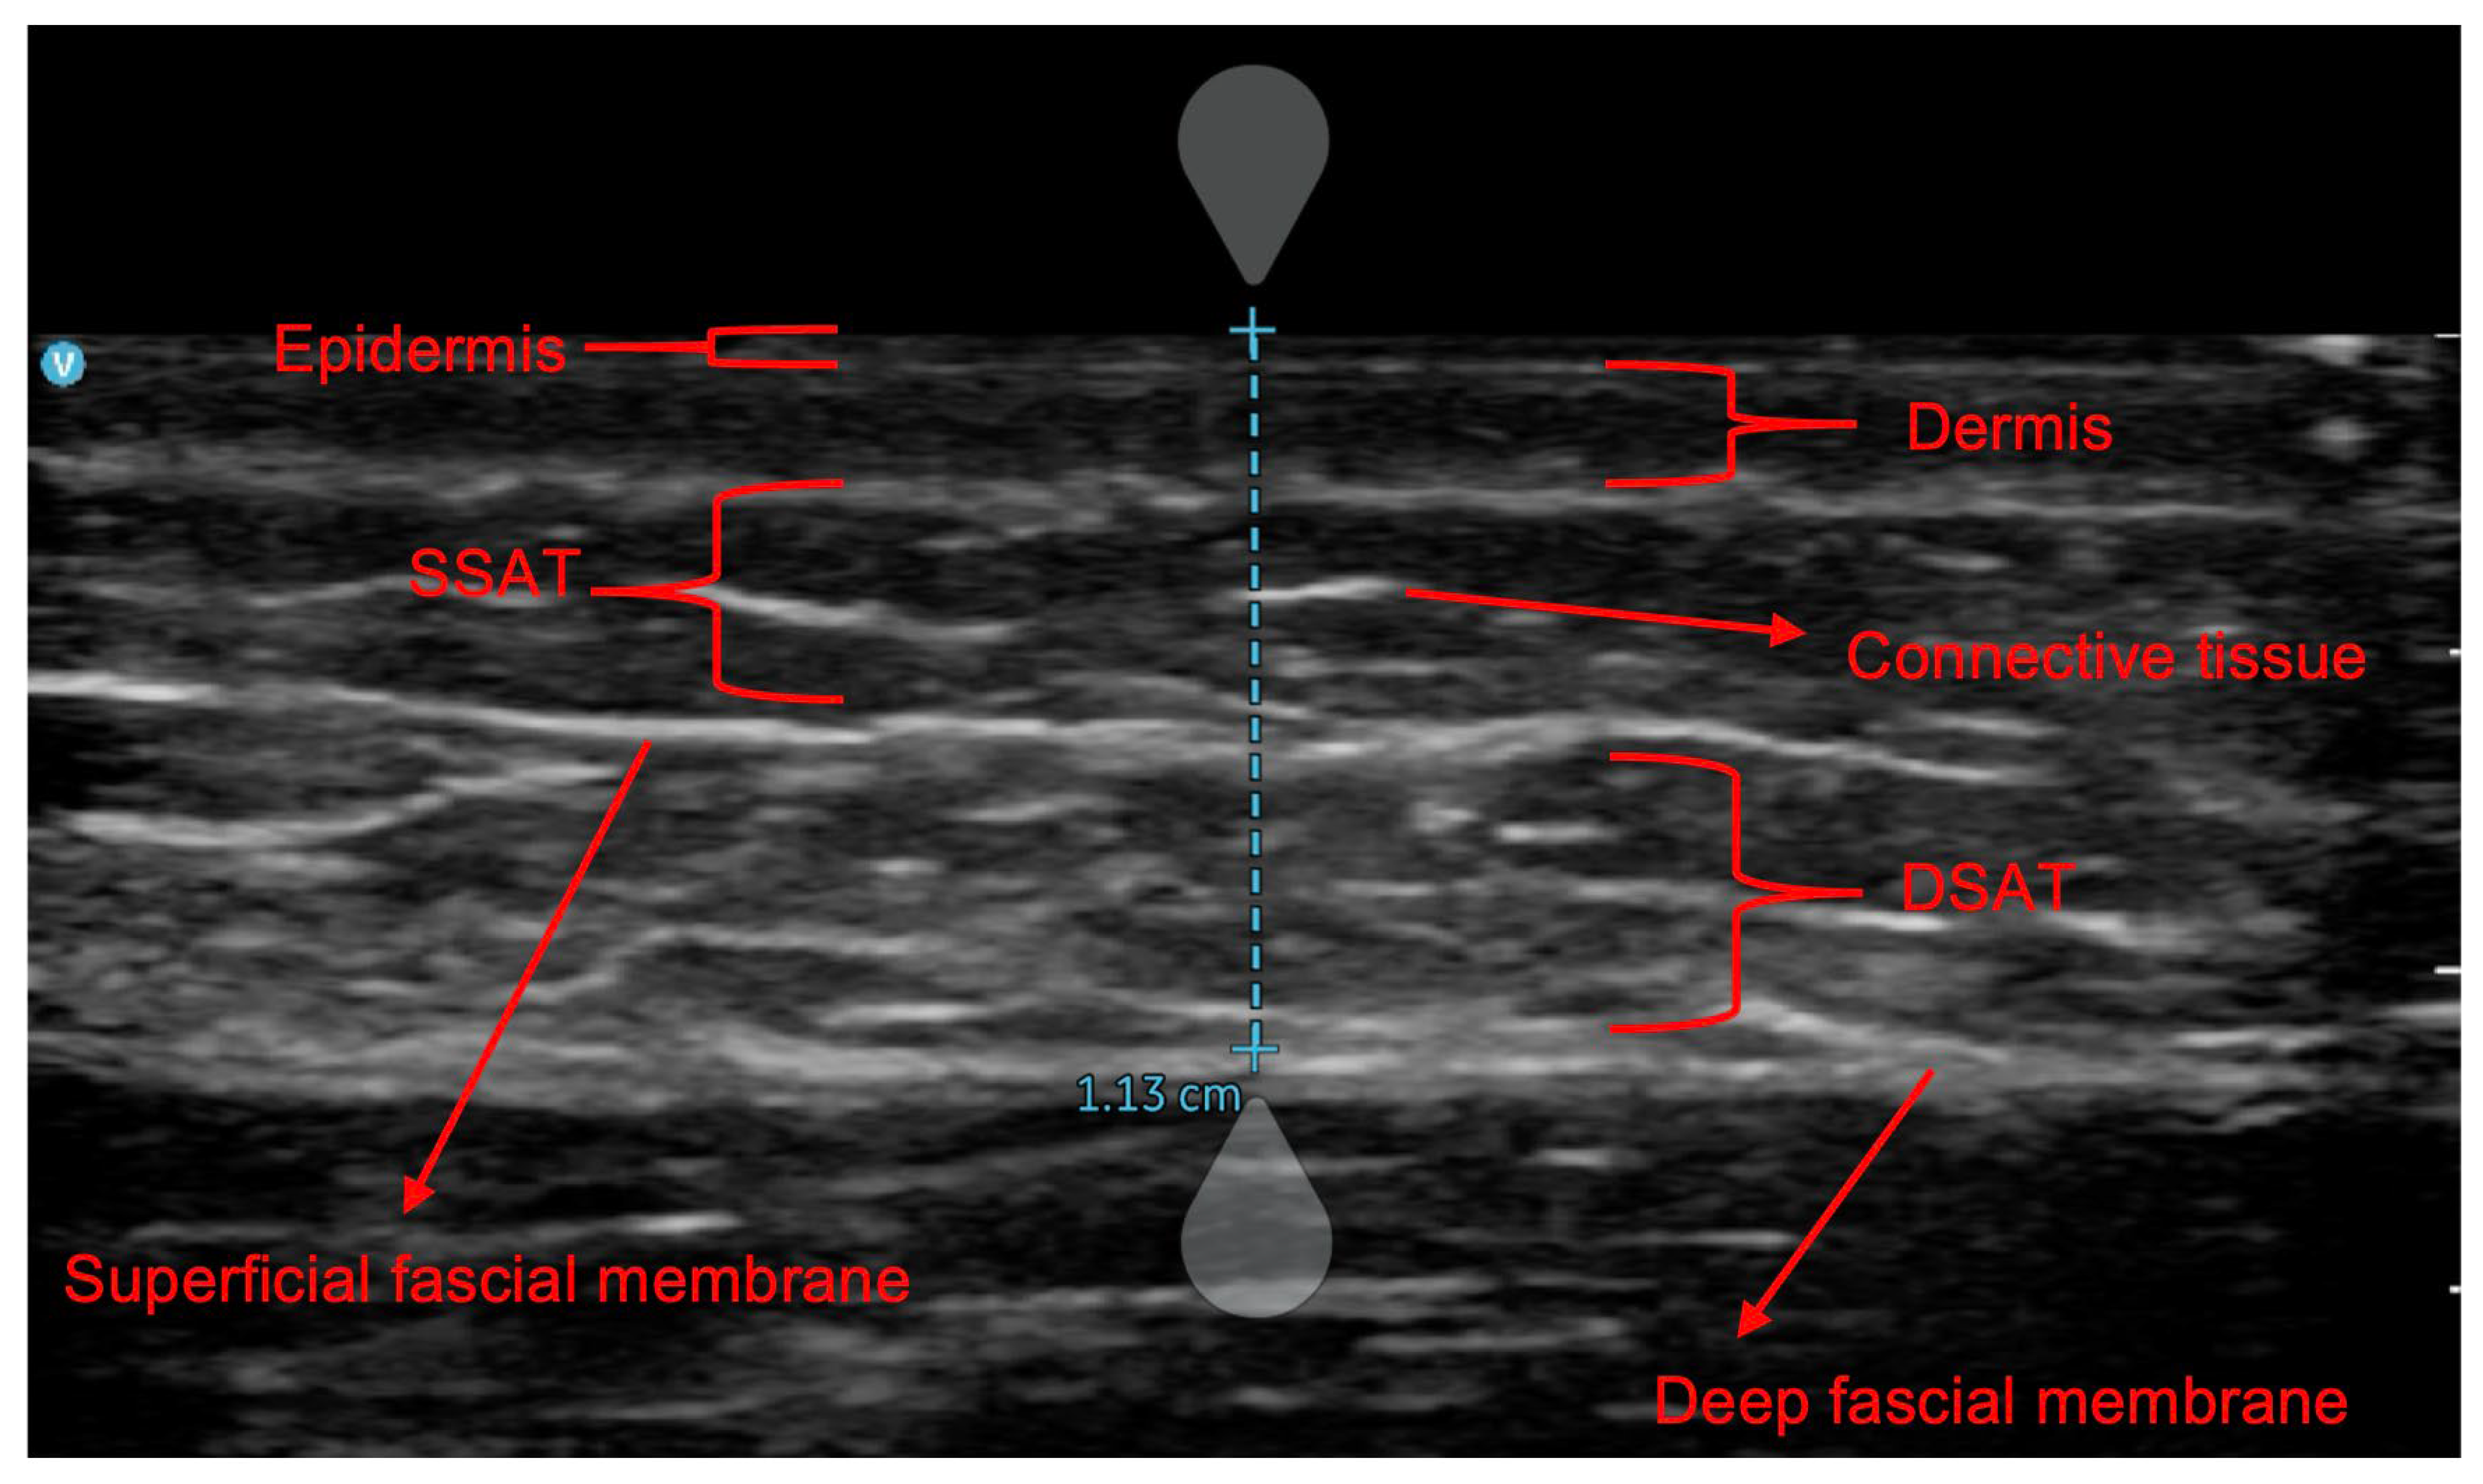

| DSAT | Deep subcutaneous adipose tissue |

| SSAT | Superficial subcutaneous adipose tissue |